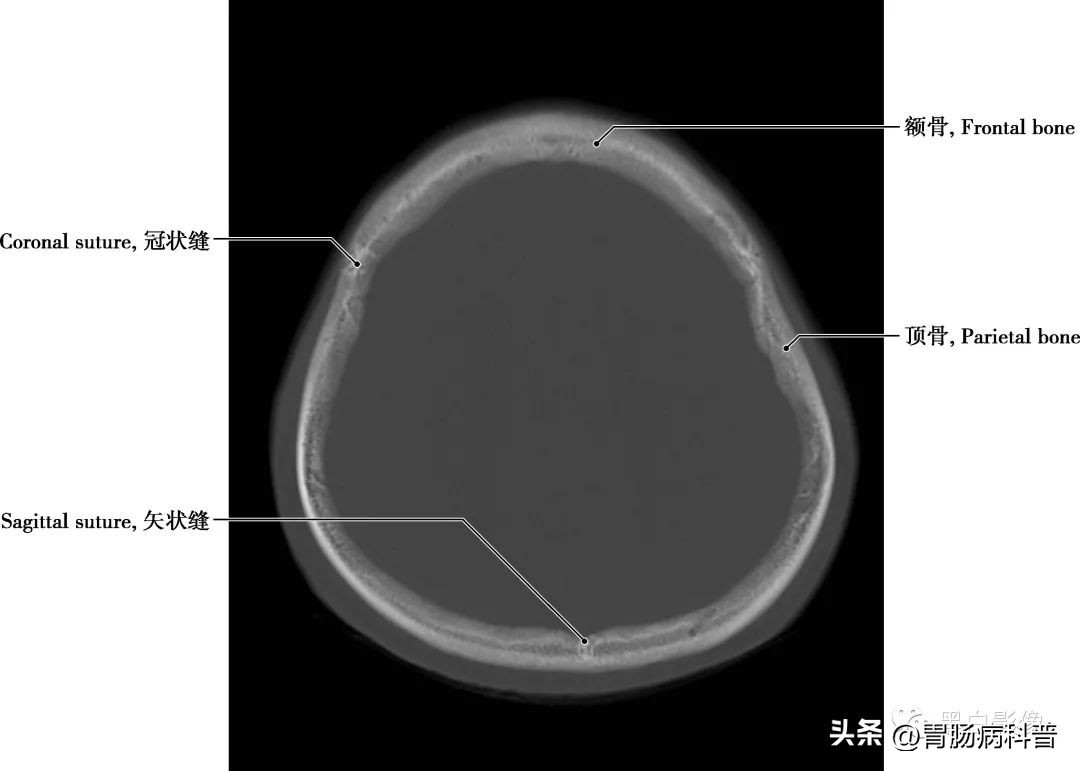

图1-2-2 经上矢状窦轴位切面

矢状缝 两顶骨之间所成的缝隙,呈矢状位走行